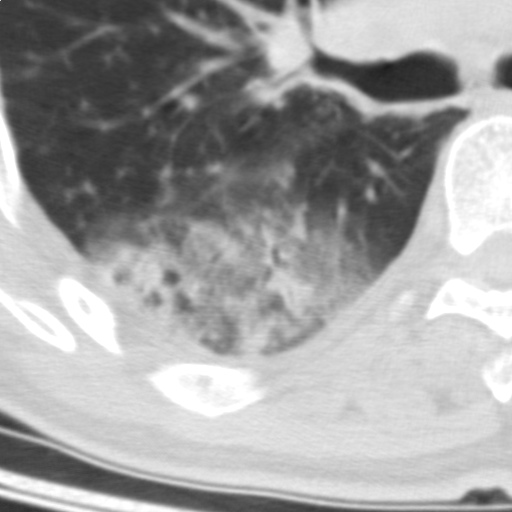

以下是引用随光逐影在2009-5-1 13:53:00的发言:[br]考虑为:1)两肺血行播散型肺结核;2)右肺下叶炎症感染。3)右侧胸膜增厚。